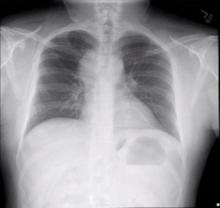

At the end of the procedure, the patient was extubated on table and then recovered in the PACU. A chest x-ray did not reveal any residual pneumothorax. The Blake drain was removed on the first post-operative day and the patient was discharged home.